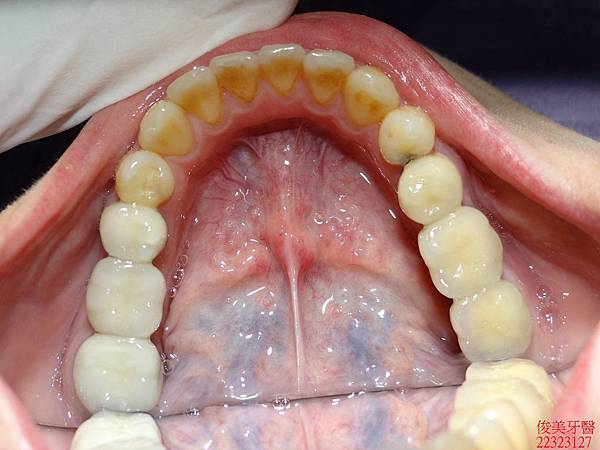

上排牙齒已有延長的現象,牙縫更容易塞東西,且沒有咀嚼功能。

蛀牙過多,且深。牙弓形狀已非標準形態。

下顎狀況 。